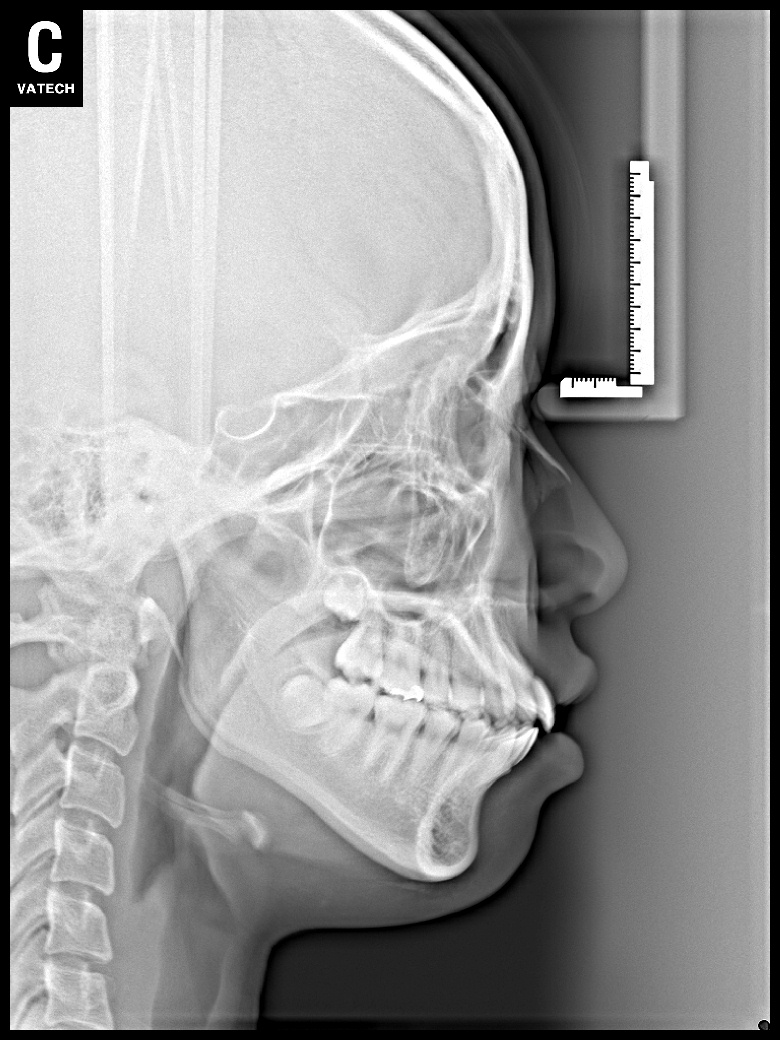

치료 후 사진입니다.